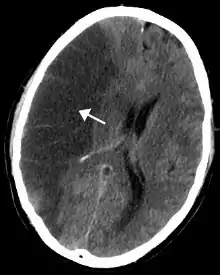

Hipertensión intracraneal idiopática

La hipertensión intracraneal idiopática, o presión alta inexplicable en el cráneo, es una afección rara que puede causar discapacidad visual, dolor de cabeza intenso frecuente y tinnitus. Se observa con mayor frecuencia en mujeres obesas, y la incidencia de hipertensión intracraneal idiopática está aumentando junto con el número de personas obesas.[46][47]